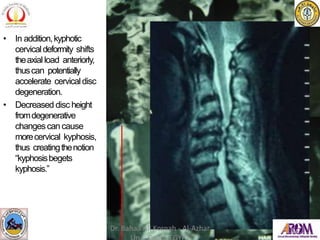

• In addition,kyphotic

cervicaldeformity shifts

theaxial load anteriorly,

thuscan potentially

accelerate cervicaldisc

degeneration.

• Decreased disc height

fromdegenerative

changescan cause

morecervical kyphosis,

thus creatingthenotion

“kyphosisbegets

kyphosis.”